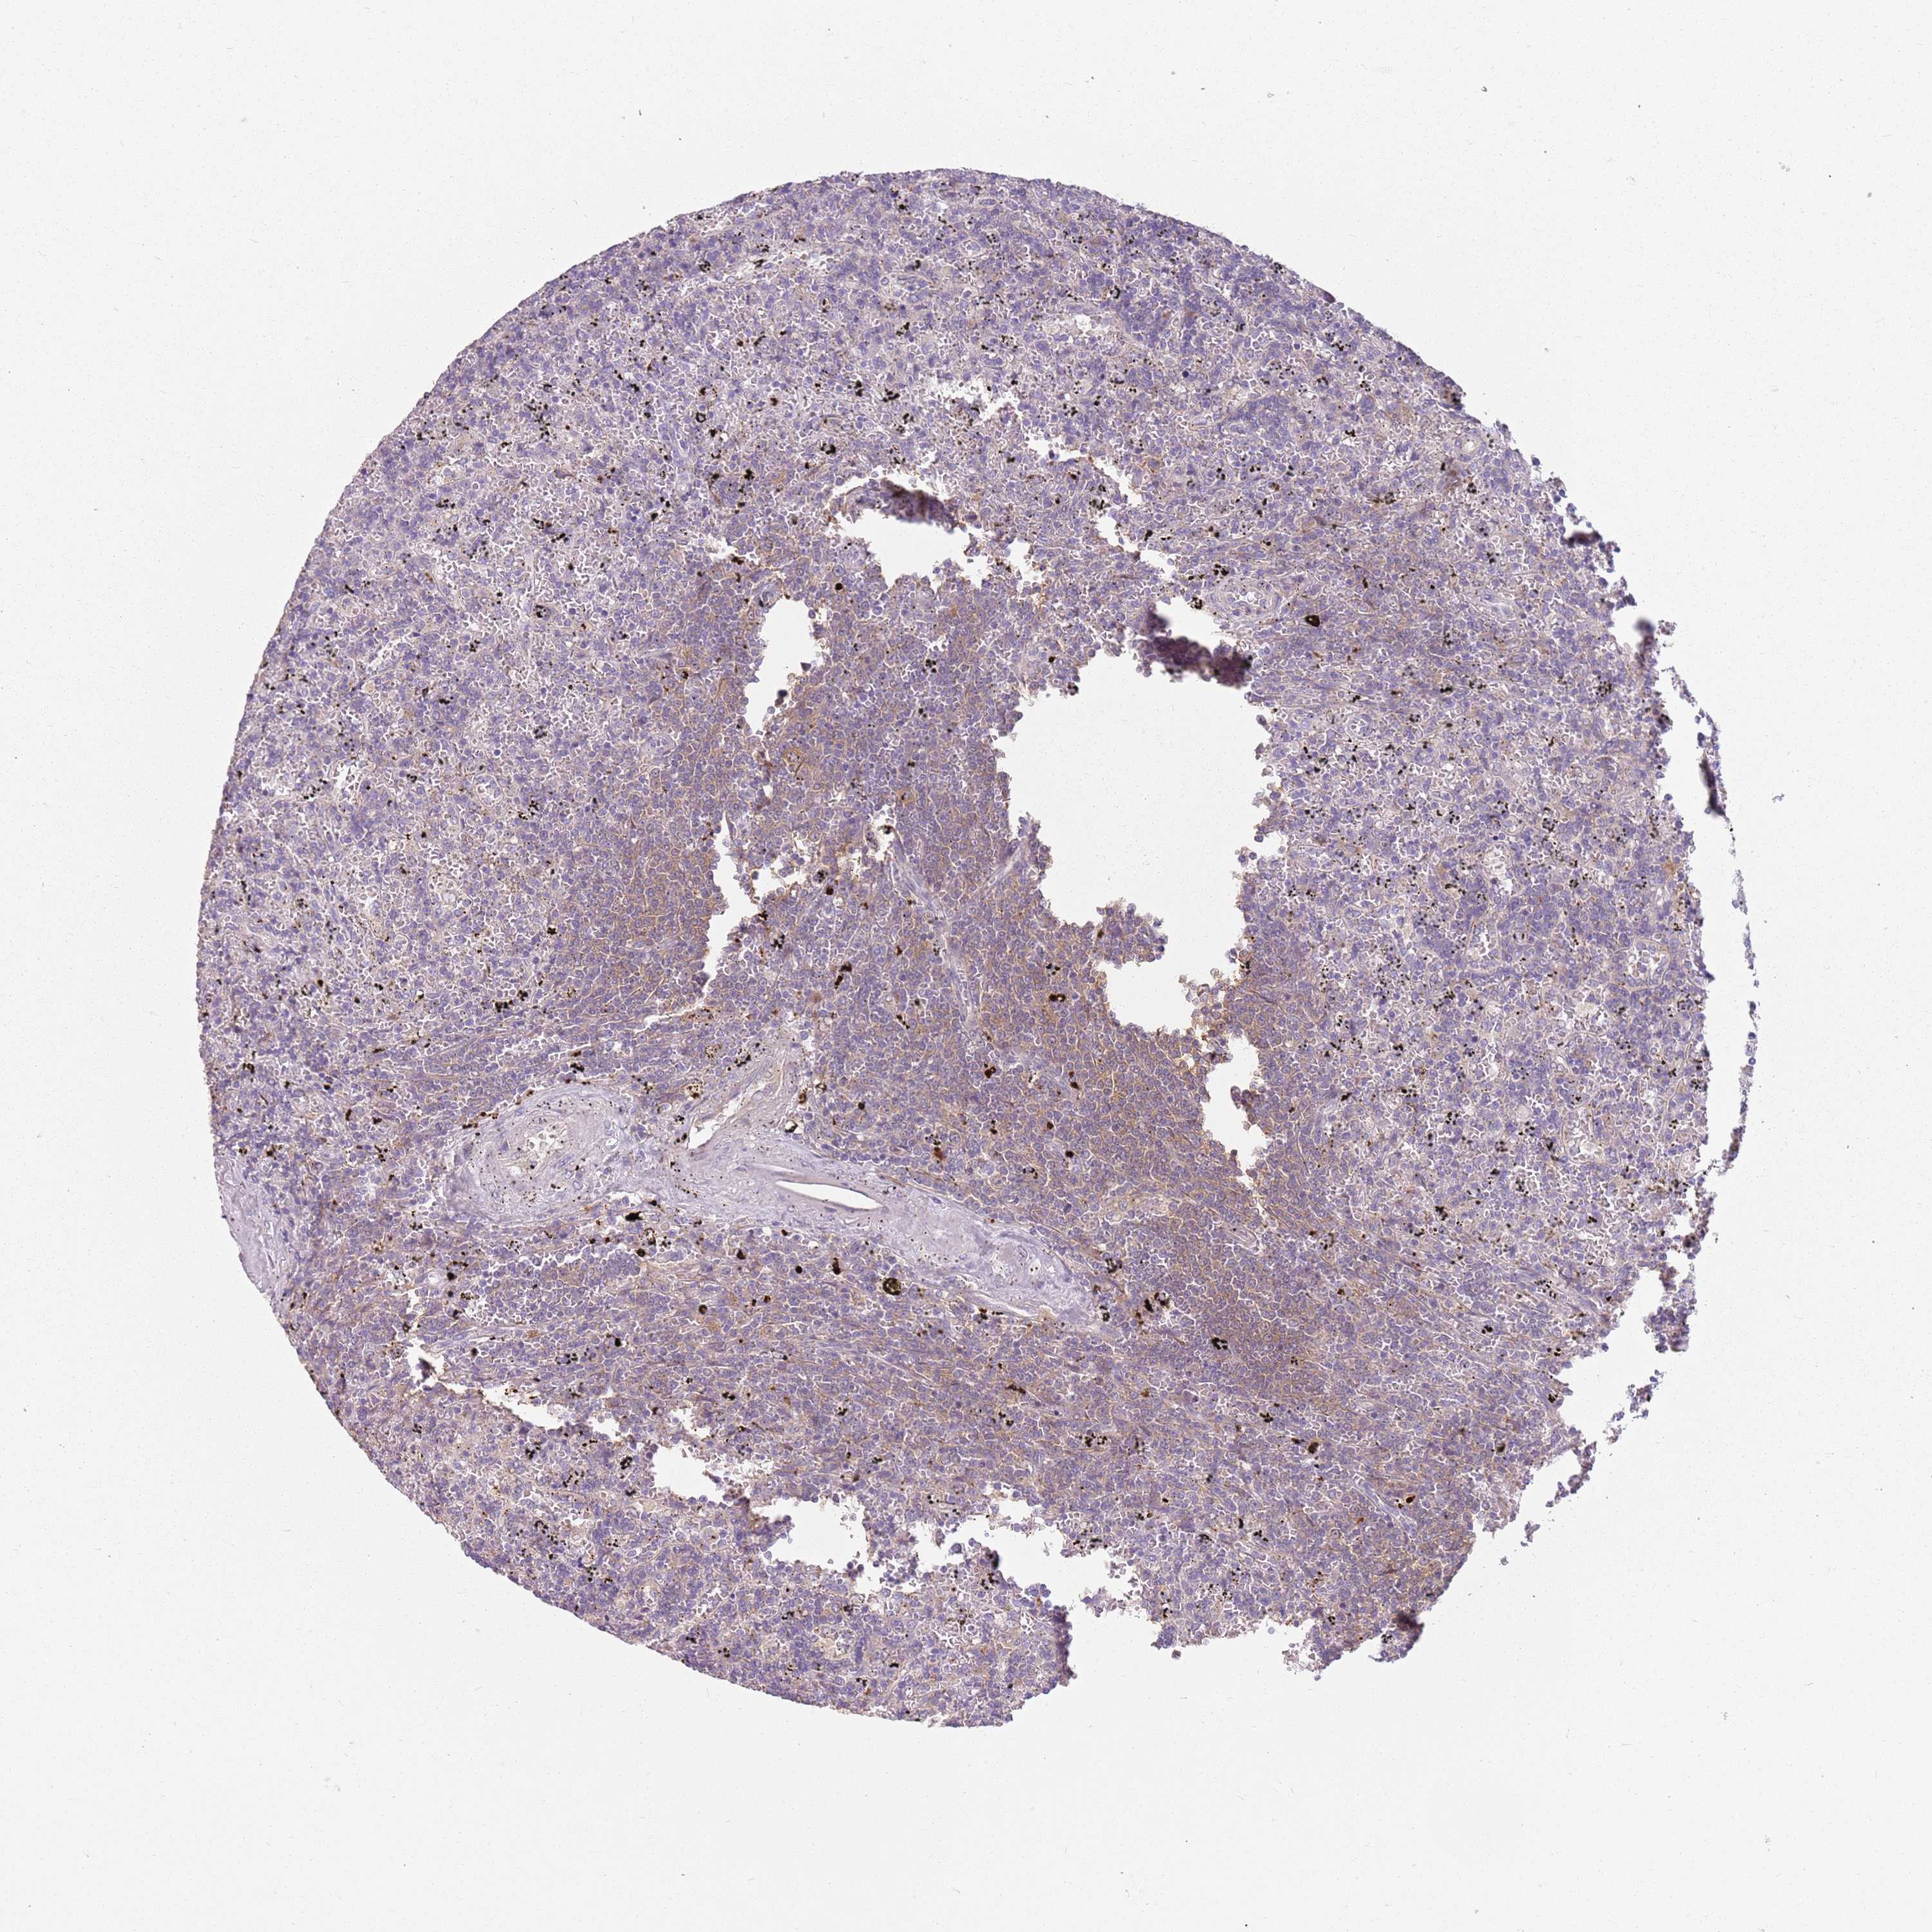

LYMPHOMA - Protein expressioni

A mouse-over function shows sample information and annotation data. Click on an image to view it in a full screen mode. Samples can be filtered based on level of antibody staining by selecting one or several of the following categories: high, medium, low and not detected. The assay and annotation is described here.

Antibody stainingi

Antibody staining in the annotated cell types in the current human tissue is reported as not detected, low, medium, or high, based on conventional immunohistochemistry profiling in selected tissues. This score is based on the combination of the staining intensity and fraction of stained cells.

Each image is clickable and will lead to virtual microscopy that enables deeper exploration of all samples and also displays staining intensity scores, fraction scores and subcellular localization as well as patient and tissue information for each sample.

Antibody HPA047132

Staining

High

Medium

Low

Not detected

Intensity

Strong

Moderate

Weak

Negative

Quantity

>75%

75%-25%

<25%

None

Location

Nuclear

Cytoplasmic/membranous

Cytoplasmic/membranous,nuclear

Hodgkin's disease, NOS

Malignant lymphoma, non-Hodgkin's type, High grade

Malignant lymphoma, non-Hodgkin's type, Low grade